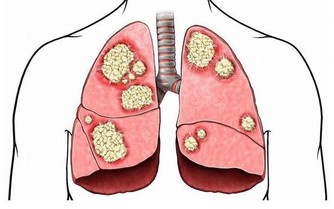

抗生素

抗生素並非不是好藥,只是現在有些濫用。抗生素,包括口服藥,輸液、打針藥,藥物本身即損傷陽氣。尤其冬季輸液更傷陽氣,室外溫度本來就低,遠遠低於體溫,寒涼的藥液滴入血管內,陰寒隨之進入內臟,需要人體陽氣去溫煦氣化,這樣就可能導致傷陽太甚。